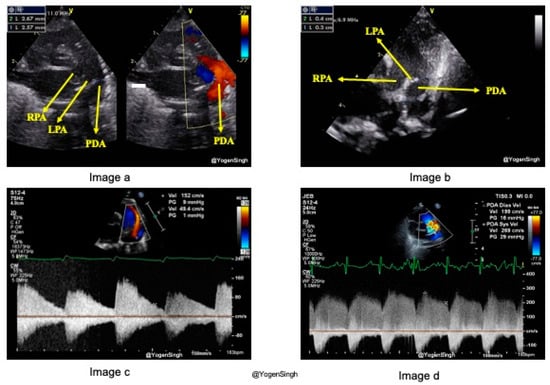

3.1.1. PDA Size

Describing the size of PDA as small, moderate, or large over-simplifies the echocardiographic evaluation of ductal characteristics, its morphology, and hemodynamic impact. PDA size is measured from the transductal diameter at the site of maximum constriction, most commonly seen at the pulmonary end (Figure 3a). PDA is not a straight symmetric tubular vessel, but it has six different types of morphologies and is tortuous at times (Figure 3b). PDA constriction leading to closure can occur at any segment of the ductus arteriosus, although commonly seen at the pulmonary end [17,18]. The standard echocardiography views to measure the size of a PDA are: (1) high left-sided parasternal “ductal” view, or (2) suprasternal ductal cut view. A PDA’s size can be measured on a 2D image or using Color Doppler (color flow mapping). Color Doppler can be used to highlight the PDA’s size for better visualization. However, the color gain setting should be optimized to avoid color “bleeding” out of the vessel lumen, leading to overestimating the PDA diameter. A PDA diameter of >2 mm is generally considered large in preterm infants.

3.1.2. PDA Shunt Direction

The flow direction across PDA depends upon the gradient between pulmonary and systemic pressures and the interplay between systemic and pulmonary vascular resistance. By convention, blood flow from the aorta to the pulmonary artery is left-to-right when systemic pressure is higher than pulmonary pressure, and the magnitude of blood flow mostly correlates with the hsPDA. When the PVR is high or in certain CHDs (such as interrupted aortic arch), the PDA flow can be bidirectional or right-to-left. The direction of the ductal shunt is assessed using Color Doppler. In a conventional echocardiography setting, the left-to-right shunt across the PDA on a high parasternal ductal view is seen as a red jet (Figure 3a), while a right-to-left ductal flow is seen as blue in color. The Doppler assessment shows a left-to-right shunt above the baseline (toward the probe), while the right-to-left shunt is seen below the baseline (away from the probe) [17,19].

3.1.3. PDA Shunt Velocity and Pattern

The clinical and hemodynamic significance of PDA depends on the dynamics of blood flow across the ductus, which is contingent upon factors such as the pressure gradient, vessel dimensions, vessel length, and blood viscosity. The Doppler assessment of flow velocity (volume per unit time) and flow patterns across the PDA offers invaluable insights. A lower pressure gradient between systemic and pulmonary circulation or a large PDA allows blood to flow at a lower velocity through the ductus, resulting in a non-restrictive or pulsatile shunt flow pattern characterized by low peak systolic velocity and a very low diastolic velocity (<50 of peak systolic velocity) (Figure 3c). Conversely, as a PDA is constricting or closing, a higher peak velocity is seen across the constricting segment, known as a restrictive or constricting flow pattern (Figure 3d) [20]. The shunt velocity varies during the cardiac cycle. If the end-diastolic velocity exceeds 50% of the peak systolic velocity, it is considered a constricting flow pattern. The flow velocity can be obtained by applying pulsed or continuous wave Doppler within the PDA. Although pulsed wave Doppler is specific (Figure 2), continuous wave Doppler has to be applied to avoid aliasing when the velocity is >2 m/s.

Figure 3. Characteristics of patent ductus arteriosus (PDA). (a) shows the measurement of PDA simultaneously on 2D and color flow mapping. (b) shows the measurement of a tortuous PDA in 2D; the narrowest part should be reported. (c) shows the pulsatile flow pattern on Doppler assessment, and (d) shows a constricting flow pattern. LPA—left pulmonary artery, RPA—right pulmonary artery, PDA—patent ductus arteriosus.